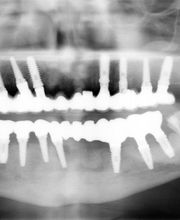

Desde hace 25 años , fuimos pioneros en nuestro pais en aplicar implantes en rehabilitaciones de pacientes con implantes dentales, miles de pacientes disfrutan desde entonces de estos avances. Nuestros trabajos han sido premiados en congresos internacionales de la especialidad, diseñamos una técnica denominada Esbipro e inventamos unos instrumentos, los expansores roscados de hueso, para poder insertar implantes en condiciones donde no era pposible insertar implantes. Nuestros trabajos han sido publicados por dos de las sociedades científicas más reconocidas mundialmente, la Asociación Norteamericana de cirugía maxilofacial y la Asociación Norteamericana de disfunción craneomandibular. Todos los avances que se han venido produciendo en nuestra especialidad se ha ido incorporando a nuestra praxis, Microscopio, Láser, RESONANCIA CUANTICA MOLECULAR, cirugía ósea piezoelectrica, Gás de la Risa,Esterilización ciclo B,Panorámica digital y TAC.